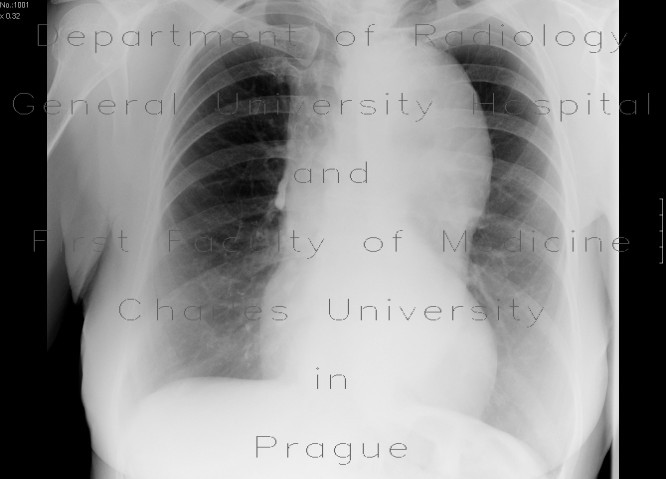

RTG hrudníku

Základní vyšetřovací metoda, vstupní vyšetření u všech pacientů s podezřením na onemocnění srdce. Vstoje se RTG hrudníku provádí v PA projekci (srdce je blíže detektoru, je lepší ostrost a nedochází k tak velkému zkreslení velikosti), ev. s doplněním bočné projekce. Na snímku sledujeme:

- konfiguraci srdečního stínu: zvětšení celého srdce (srdeční selhání, perikardiální výpotek), jednotlivých oddílů, kalcifikace v srdečním skeletu, hrotovém aneurysmatu,

Podrobnější informace naleznete na stránce Srdeční stín. - náplň plicních žil: městnání, hyperémie,

- šíře plicních tepen: pulmonální oblouček, rozšíření truncus intermedius, "amputace hilů" (u plicní hypertenze),

- aortální oblouk: elongace či vinutá hrudní aorta a ateromy u aterosklerózy, rozšíření u aneurysmatu, zmenšení při rotaci srdce doleva (u zvětšení pravé komory),

- pleurální výpotek: přítomnost pleurálního výpotku např. u srdečního selhání,

- plicní parenchym: alveolární či intersticiální plicní edém, Kerleyovy linie,

- invaze: kardiostimulátor a poloha jeho elektrod, centrální žilní katetr, kontrapulzace, Swan-Ganzův katetr, umělé chlopně, kličky sutury sternotomie, drobné kovové svorky v průběhu bypassu.

Pro orientační hodnocení šíře srdečního stínu na PA snímku hrudníku vstoje slouží tzv. ""kardiothorakální index"", což je poměr nejširšího rozměru srdce (latero-laterálně) a vnitřní šíře hrudníku. Kardiothorakální index nad 0,5 znamená rozšíření srdce. Toto neplatí u snímku vleže, který se provádí v AP projekci.

RTG hrudníku: kardiomegalie |